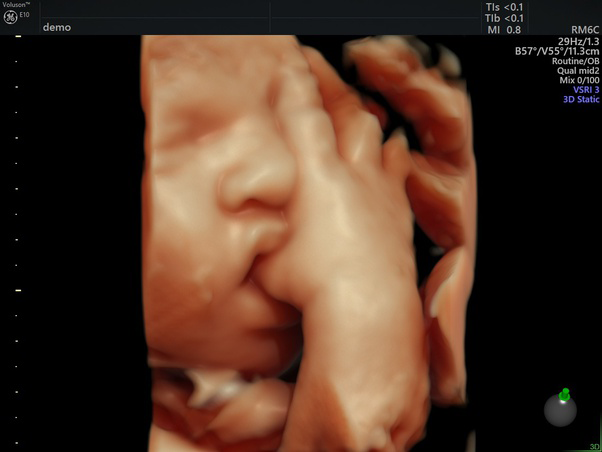

3D / 4D Scanning Baby

3D scanning og 4D scanning af din baby, kan give dig mulighed for at se din baby i utrolige detaljer, hvor I får tilsendt billeder og videoer. Her vil det endnu engang være muligt at få bekræftet jeres barns køn ved en kønsscanning. Denne scanning kan tages ​når du vil, men bedst fra uge 26-30.

3D Scanning af din baby

3D scanning af din babykan ske ​når du vil, men bedst fra uge 26-30 af graviditeten. Du kan også vælge vores avancerede 4D graviditetsscanning for at se din baby i levende farver og detaljer.

Disse 3D/4D scanninger giver en unik mulighed for at se ansigtstræk, bevægelser og føle en nærmere forbindelse til din voksende baby.

Oplev din babys ansigtstræk og bevægelser med levende detaljer i 3D, som kan styrke den følelsesmæssige forbindelse mellem dig og din baby.